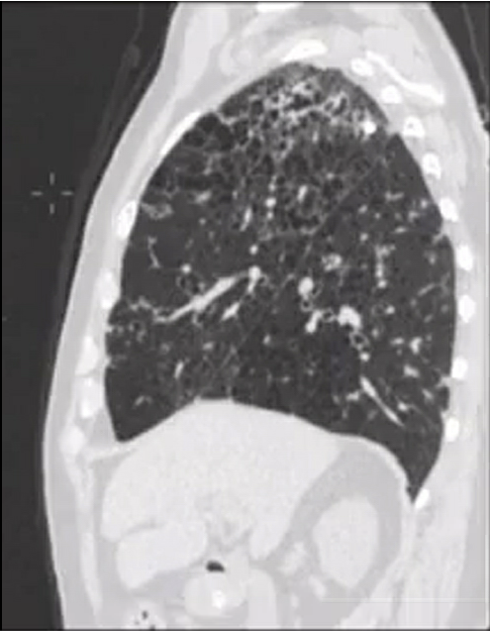

Pulmonary alveolar proteinosis

ground glass plus crazy paving

treatment = bronchoalveolar lavage

middle aged woman with chronic mild SOB. No smoking history